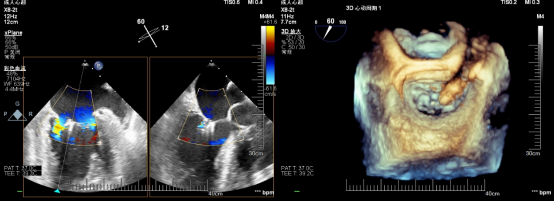

在患者全麻状态下经股静脉置管、经食道超声(TEE)引导房间隔穿刺后置入导引鞘管,手术团队将夹合器精准送达二尖瓣反流区。在TEE及X线引导下,手术团队利用二尖瓣夹(Mitraclip)准确捕获二尖瓣叶,试夹闭后经过超声证实夹闭有效,释放成型夹。术后超声评估,二尖瓣口仅见轻微反流,反流情况明显改善,患者各项生理指标正常,Mitraclip手术高质量完成。患者于术后第3天顺利出院,出院前检查患者二尖瓣反流各项参数指标恢复都超出了预期效果。

术前心超